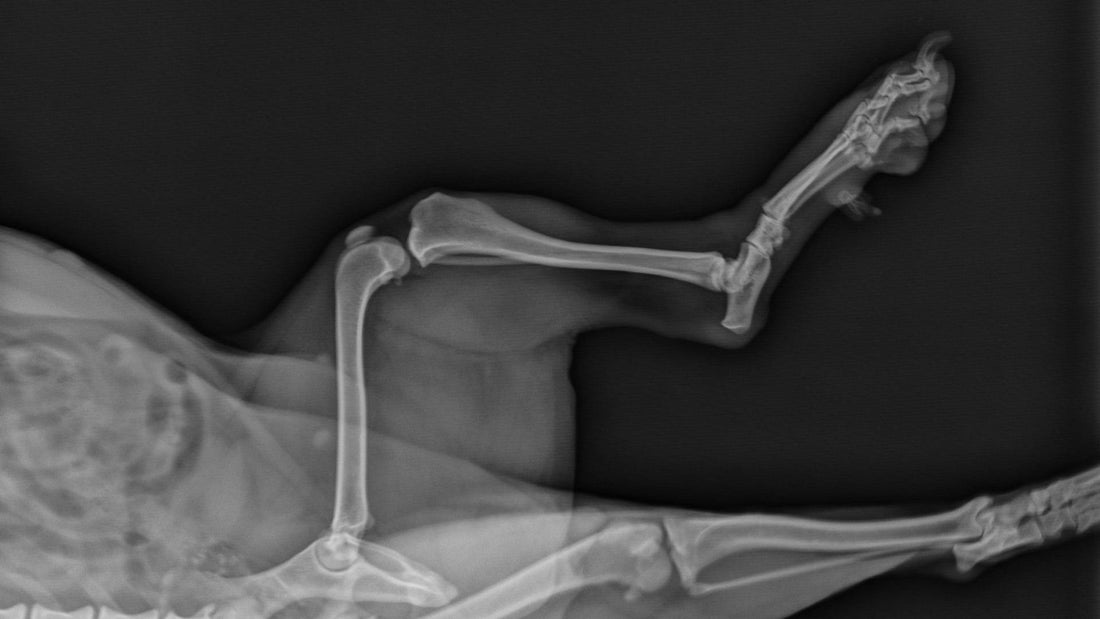

Chondroitin provides several benefits for dogs, particularly those experiencing joint pain or mobility issues. The primary benefit of chondroitin is its ability to support joint health by maintaining the integrity of cartilage. Cartilage acts as a cushion between bones in joints, allowing for smooth and pain-free movement.

- Joint Health Support: Chondroitin helps retain water in cartilage, enhancing its elasticity and shock-absorbing properties. This is particularly beneficial for older dogs or those with arthritis, as it helps maintain cartilage structure and function, reducing pain and improving mobility.

- Reduction in Pain and Inflammation: Chondroitin has anti-inflammatory properties that help reduce pain associated with joint disorders. It inhibits the production of certain enzymes that break down cartilage, thereby reducing inflammation and slowing cartilage degradation.

- Slows Progression of Osteoarthritis: For dogs suffering from osteoarthritis, a progressive and degenerative joint disease, chondroitin can help slow down the progression of the disease. By maintaining healthy cartilage and reducing inflammation, chondroitin can help improve the quality of life for dogs with chronic joint conditions.

Chondroitin works by supporting the structure and function of cartilage in a dog’s joints. Cartilage is made up of a network of collagen fibres and other molecules that trap water, making it both strong and flexible. Chondroitin sulphate, a form of chondroitin, is one of these critical molecules.

- Water Retention in Cartilage: Chondroitin enhances the ability of cartilage to retain water, which is essential for its elasticity and shock absorption capabilities. This hydration allows the cartilage to act as an effective cushion between the bones in a joint, preventing them from rubbing against each other and causing pain.

- Inhibition of Destructive Enzymes: Chondroitin helps inhibit enzymes that break down cartilage. In dogs with arthritis or other joint disorders, these enzymes can be overly active, leading to rapid degradation of cartilage. By slowing this enzymatic activity, chondroitin helps maintain cartilage integrity and reduces further joint damage.

- Stimulation of Cartilage Repair: Chondroitin is believed to stimulate the production of glycosaminoglycans, compounds that are essential for the repair and regeneration of cartilage. This function is particularly important for dogs recovering from joint injuries or surgery.